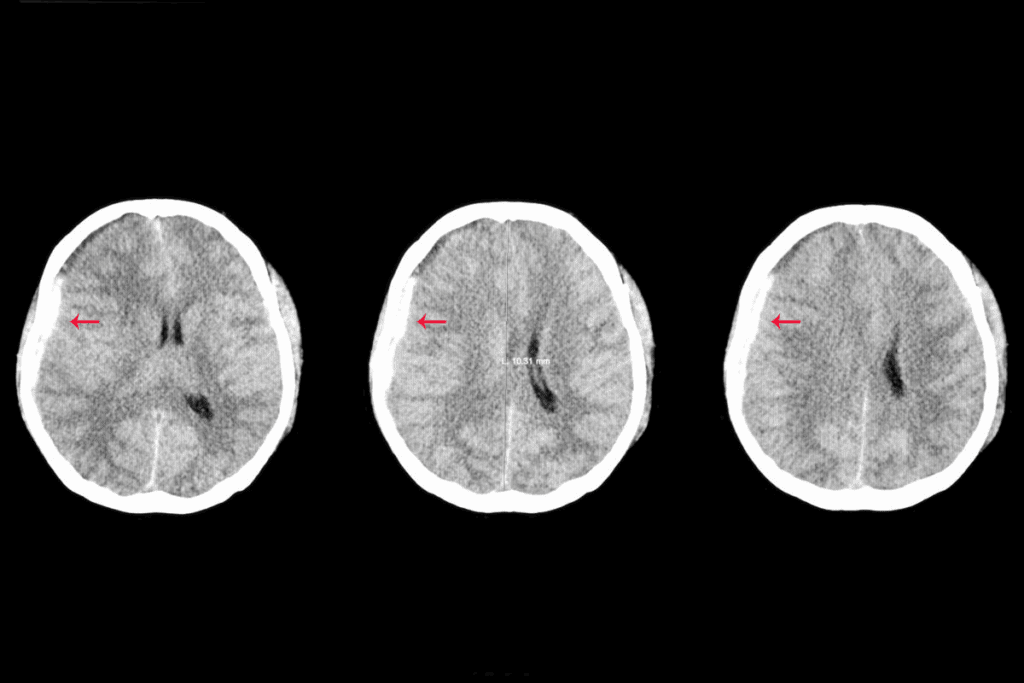

MRI and CT Scanning

Magnetic Resonance Imaging (MRI) and Computed Tomography (CT) scans are top choices for finding brain metastasis. MRI stands out because it’s very sensitive and shows soft tissues well. It’s great for spotting small tumors and those in hard-to-reach spots.

CT scans, though, are faster and easier to find. They’re good for quick checks in emergencies. But, they’re not as good as MRI for small or tricky-to-find tumors.